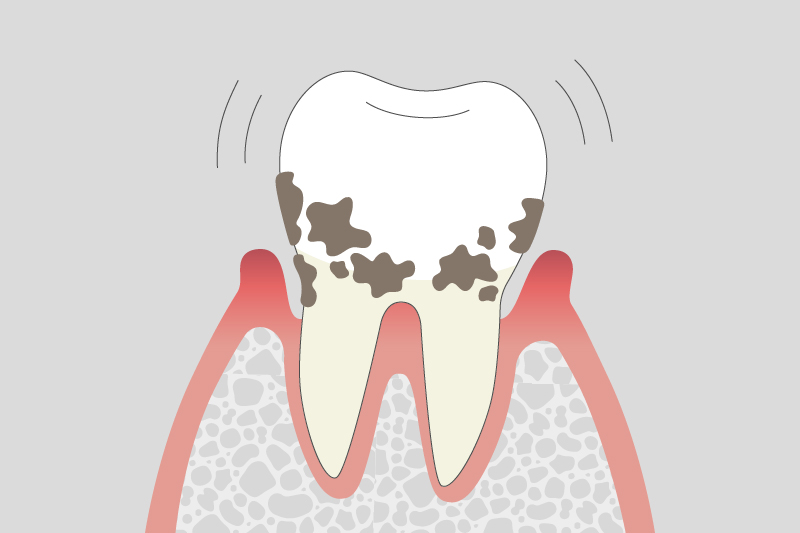

04.

重度歯周炎

歯槽骨の吸収が進み、歯の揺れが大きくなります。噛むと強い痛みが出る場合もあり、適切な治療を行わないと歯が抜ける原因となることがあります。